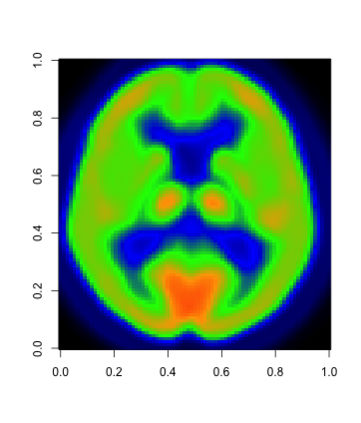

In this paper, we propose a robust estimator for the location function from multi-dimensional functional data. The proposed estimators are based on the deep neural networks with ReLU activation function. At the meanwhile, the estimators are less susceptible to outlying observations and model-misspecification. For any multi-dimensional functional data, we provide the uniform convergence rates for the proposed robust deep neural networks estimators. Simulation studies illustrate the competitive performance of the robust deep neural network estimators on regular data and their superior performance on data that contain anomalies. The proposed method is also applied to analyze 2D and 3D images of patients with Alzheimer's disease obtained from the Alzheimer Disease Neuroimaging Initiative database.